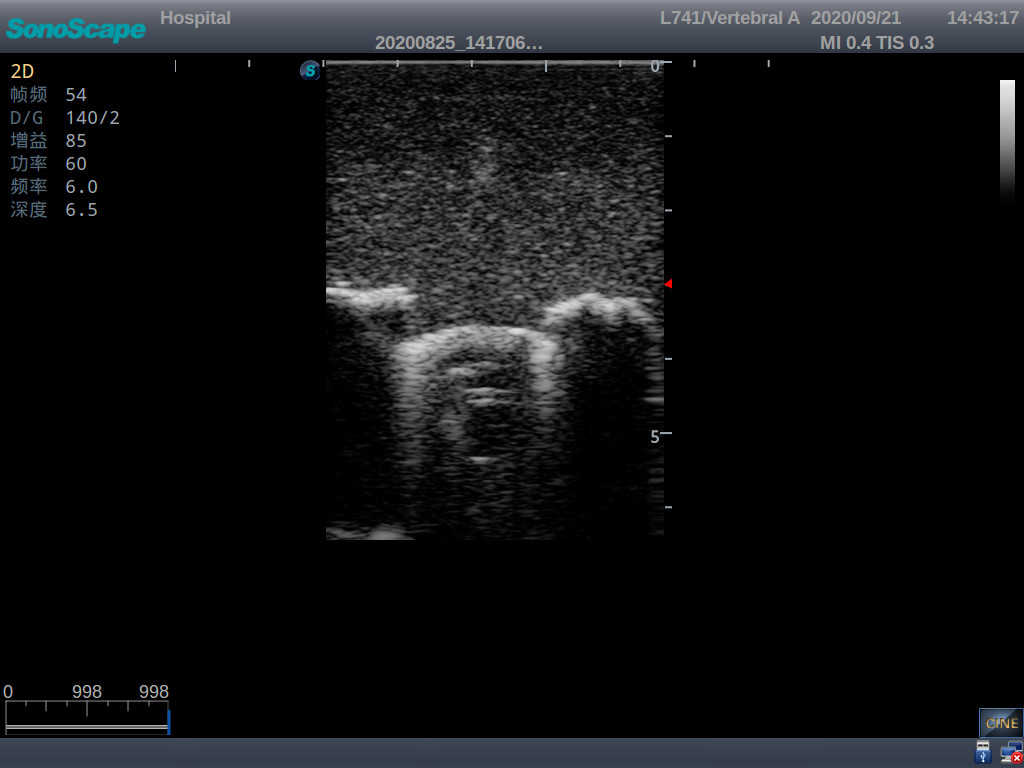

This model is an ideal choice for ultrasound-guided pediatric lumbar puncture training with true-to-life skin feel and touch, accurate anatomical structures as well as real clinical ultrasound images. Realistic resistance to needle tips and correct landmarks provide excellent hands-on experience.

2)  Real clinical ultrasound images